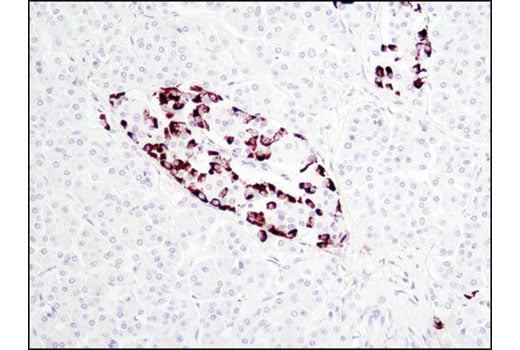

Proglucagon (D16G10) Rabbit Monoclonal Antibody #8233

• IHC

Immunohistochemistry (Paraffin) 1:400

Proglucagon (D16G10) Rabbit Monoclonal Antibody recognizes endogenous levels of total proglucagon protein.

Monoclonal antibody is produced by immunizing animals with a synthetic peptide corresponding to residues surrounding Ala137 of human proglucagon protein.

Glucose homeostasis is regulated by a variety of hormones, including glucagon. Glucagon is synthesized as the precursor molecule proglucagon and is proteolytically processed to yield the mature peptide in α cells of the pancreatic islets. Glucagon causes the release of glucose from glycogen and stimulates gluconeogenesis in the liver (1,2).